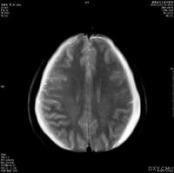

脑室炎

628健康网为您分享有关脑室炎的症状,脑室炎的治疗方法,脑室炎的预防知识,脑室炎的症状图片,脑室炎吃什么药,脑室炎怎么治...

亚急性硬膜外血肿

628健康网为您分享有关亚急性硬膜外血肿的症状,亚急性硬膜外血肿的治疗方法,亚急性硬膜外血肿的预防知识,亚急性硬膜外血...

外伤性硬膜下积液

628健康网为您分享有关外伤性硬膜下积液的症状,外伤性硬膜下积液的治疗方法,外伤性硬膜下积液的预防知识,外伤性硬膜下积...

外伤性脑脓肿

628健康网为您分享有关外伤性脑脓肿的症状,外伤性脑脓肿的治疗方法,外伤性脑脓肿的预防知识,外伤性脑脓肿的症状图片,外...

自发性脑室内出血

628健康网为您分享有关自发性脑室内出血的症状,自发性脑室内出血的治疗方法,自发性脑室内出血的预防知识,自发性脑室内出...

迟发性外伤性脑内血肿

628健康网为您分享有关迟发性外伤性脑内血肿的症状,迟发性外伤性脑内血肿的治疗方法,迟发性外伤性脑内血肿的预防知识...

急性硬脑膜下血肿

628健康网为您分享有关急性硬脑膜下血肿的症状,急性硬脑膜下血肿的治疗方法,急性硬脑膜下血肿的预防知识,急性硬脑膜下血...

慢性硬脑膜下血肿

628健康网为您分享有关慢性硬脑膜下血肿的症状,慢性硬脑膜下血肿的治疗方法,慢性硬脑膜下血肿的预防知识,慢性硬脑膜下血...

高血压性脑出血

628健康网为您分享有关高血压性脑出血的症状,高血压性脑出血的治疗方法,高血压性脑出血的预防知识,高血压性脑出血的症状...